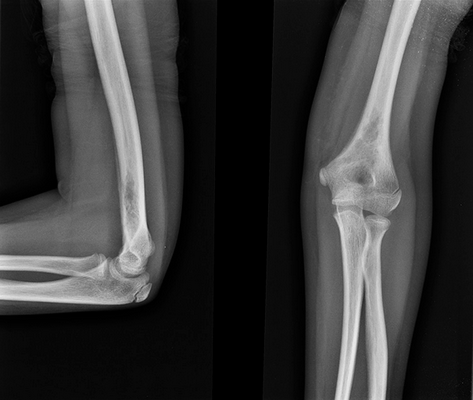

На рентгеновских снимках эозинофильная гранулема имеет вид литического очага округлой или овальной формы с четкими границами, расположенного преимущественно в костномозговой полости. При этом его размеры могут варьироваться в широких пределах. Как правило, признаки перифокального склероза отсутствуют. При поражении губчатой кости наблюдается так называемый пробойниковый дефект, а при локализации в позвоночнике может наблюдаться клиновидная деформация или формирование плоского позвонка. Таким образом, рентгенологическая картина при эозинофильной гранулеме не имеет специфических черт и во многом схожа с саркомой Юинга, остеогенной саркомой и другими злокачественными образованиями.

- Рентгенография костей. При рентгенологическом исследовании определяются единичные или множественные опухолевидные образования, участки деструкции, которые могут располагаться как в трубчатых, так и в плоских костях. При подозрении на эозинофильную гранулему обязательно проводят рентгенографию челюстей.